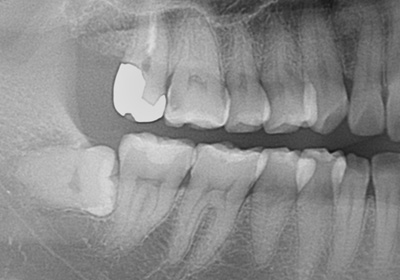

水平埋伏歯レントゲン像